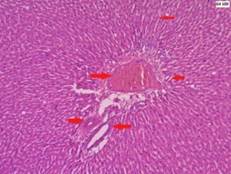

Fig. 7: G410X HandE stain architecture of liver showing prominent hapatocytes separated by dilated sinusoids

Fig. 8: G4 40X HandE stain architecture of liver showing prominent hapatocytes separated by dilated sinusoids

Fig. 1 and 2, G1 (Group 1) 10X and 40X HandE stain histopathology section of liver shown normal hepatic architecture compressed of hepatic lobules formed by the central vein and the cords of hepatocytes with indistinct sinusoidal dilatation in fig. 3,4,7and8. G2and4 (Group 2and4)10X and 40X HandE stain shown prominent sinusoidal dilatation.

G4 (group 4) Bark extract of Terminalia arjuna (500 mg/Kg body weight) treated rats histopathology section of liver shown normal hepatic architecture

We observed marked structural alteration, i.e. microvescicular and macrovesicular fatty changes in histopathology of liver of rats fed with high fat diet. Hyper lipidemic rats treated with ethanolic extract of Terminalia arjuna is shown normal architecture of liver histology. Ragavan, B., et al. reported in their study, high fat diet induced rat treated with Terminalia arjuna bark extract shown to partially reverse the damage (Fatty changes) [16].